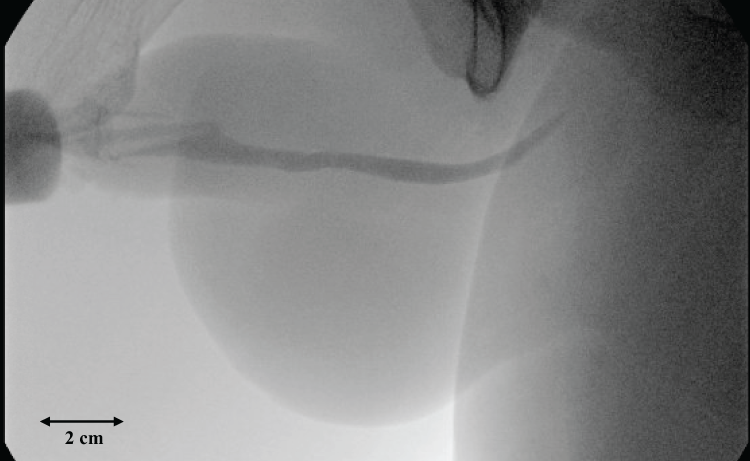

Postoperative RUG was performed at 4 weeks post-operatively demonstrated no extravasation, and the Foley catheter was removed (Figure 3).

Figure 3: Office peri-catheter RUG performed at 4 weeks post-operatively demonstrating a healed urethra without extravasation or stricture